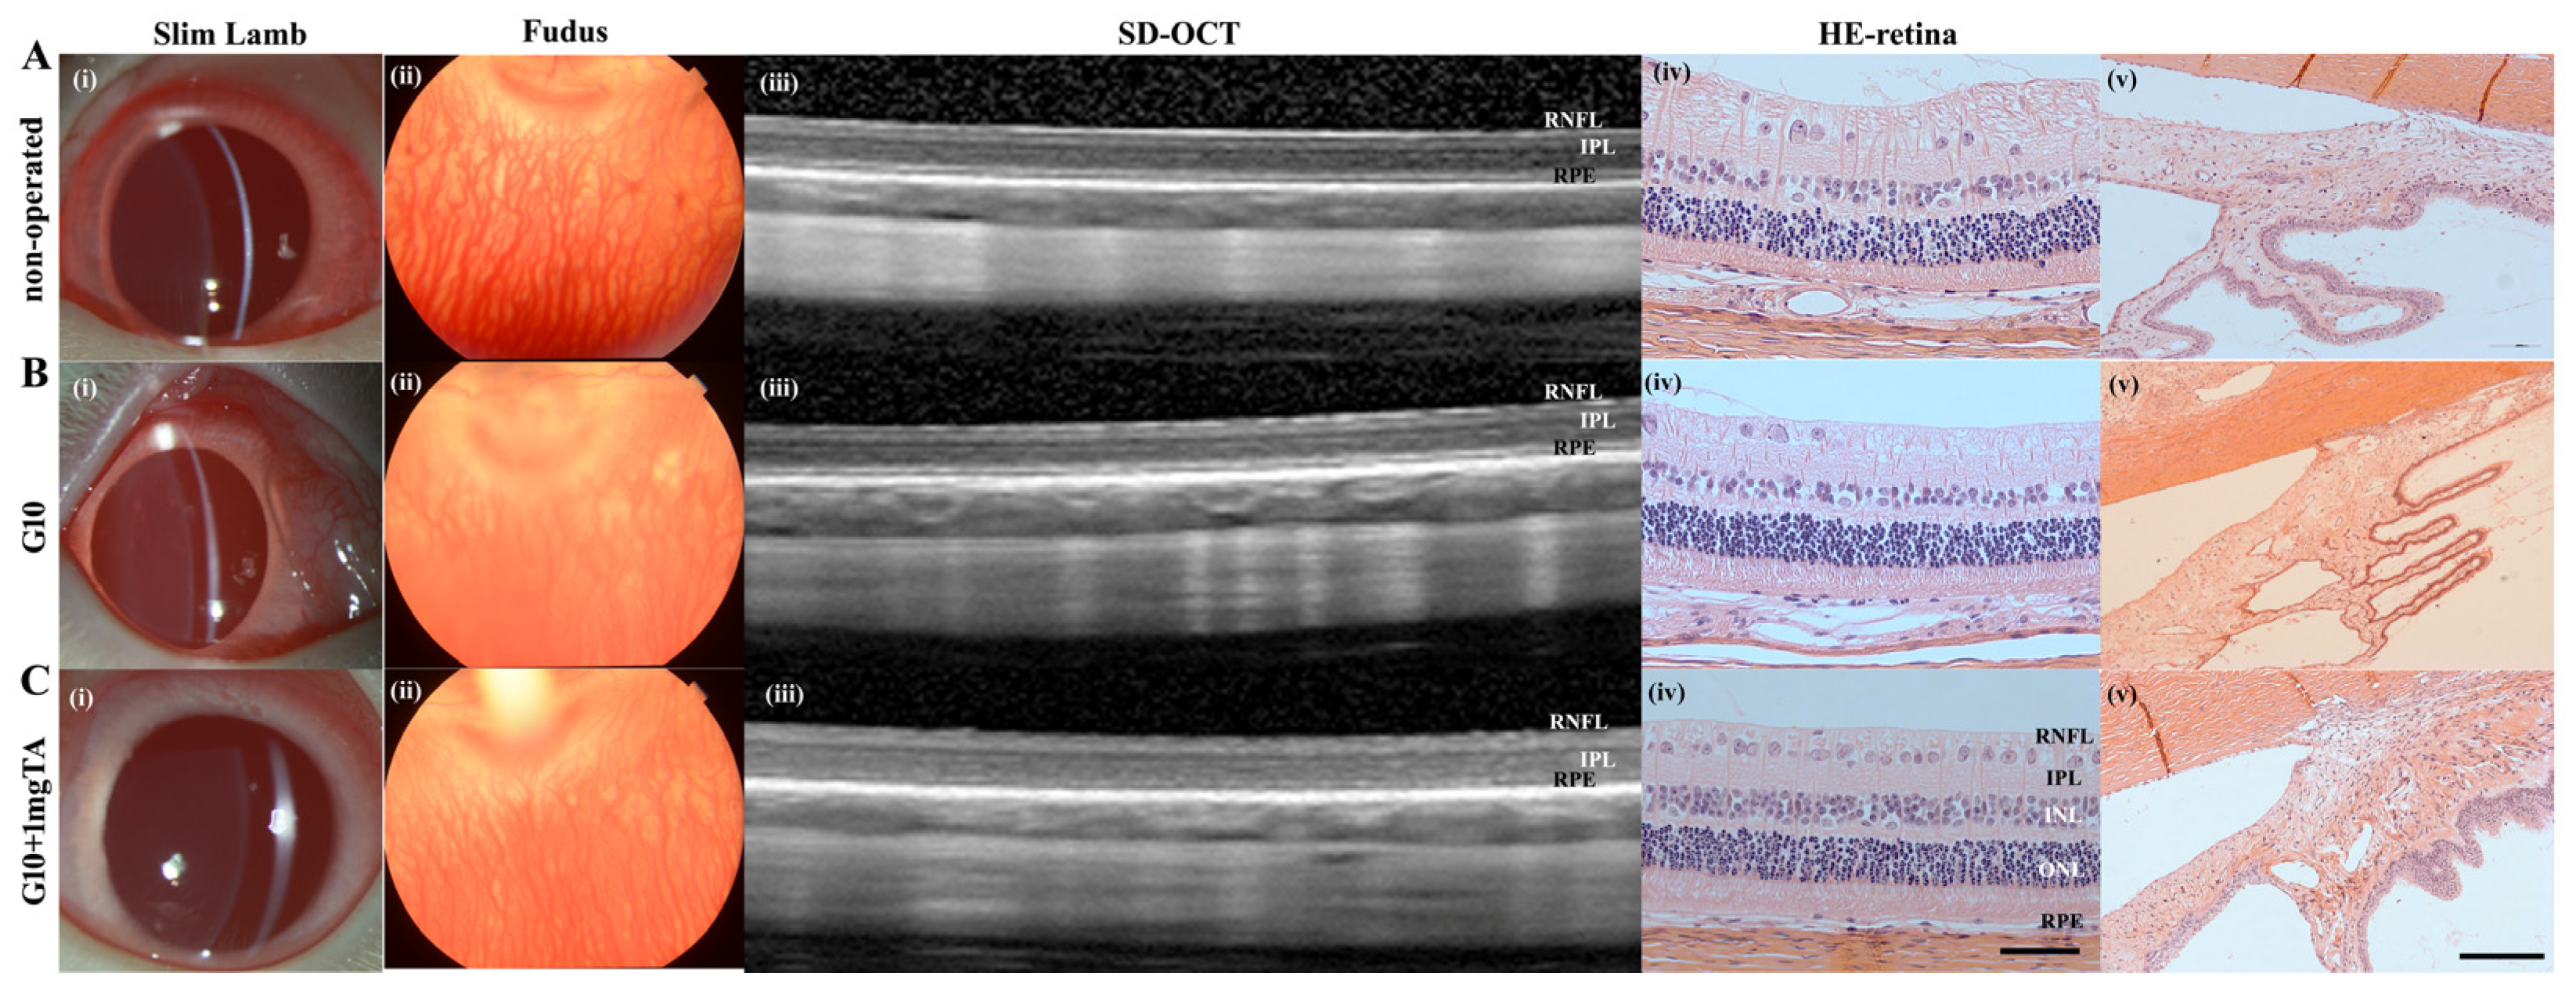

As assessed by slit lamp examination and fundus evaluation, rabbits whose eyes had been implanted with G10 or G10 + 1 mg TA hydrogels showed no significant inflammation in either the anterior or posterior segment of the eye (columns (i–iii) in Figure 6A–C) and had normal IOP. Furthermore, 10% GelMA demonstrated superior long-term biocompatibility (2 months) in vivo; the injected eyes presented clear corneas, absence of cataracts (Figure 7(Bi)), normal IOP (between 6 and 15 mmHg, Figure 8C), and normal retinal thickness and choroid thickness as determined by both SD-OCT and H&E histology (Figure 7(Biii,Biv); Figure 8A,B). Compared with the non-operated group, the eyes of the G10 and G10 + 1 mg TA groups displayed no disorganized microstructure, apparent inflammatory cells, hemorrhage, or edema two months after injection of the hydrogel (Figure 7A–C). No inflammatory cells were found in the anterior chamber angle in any of the sections examined (Column (v) in Figure 7A–C). These results indicate that the functions of the entire layer of neuroretinal tissue were normal in GelMA-injected eyes. Furthermore, normal IOP values were observed in eyes injected with G10 and G10 + 1 mg TA for 2 months after injection (Figure 8C).

Figure 7.

In vivo imaging and ex vivo retinal analysis of rabbits 2 months after implantation of GelMA hydrogels. (A–C), Column (i): slit-lamp images of operated BSS controls and G10 and G10 + 1 mg TA-injected eyes, showing no significant inflammation or cataract formation. Column (ii): images of the fundus revealing normal optic disc appearance and vessel morphology in all groups. Column (iii): SD-OCT images obtained in all four groups revealed no reduction in retinal thickness from the RPE to the RNFL. Column (iv): H&E histology analysis was performed in all three groups, and the results were consistent with the OCT findings (scale bars, 50 μm). Column (v): H&E histological analysis of the anterior chamber angle (scale bars, 50 μm).